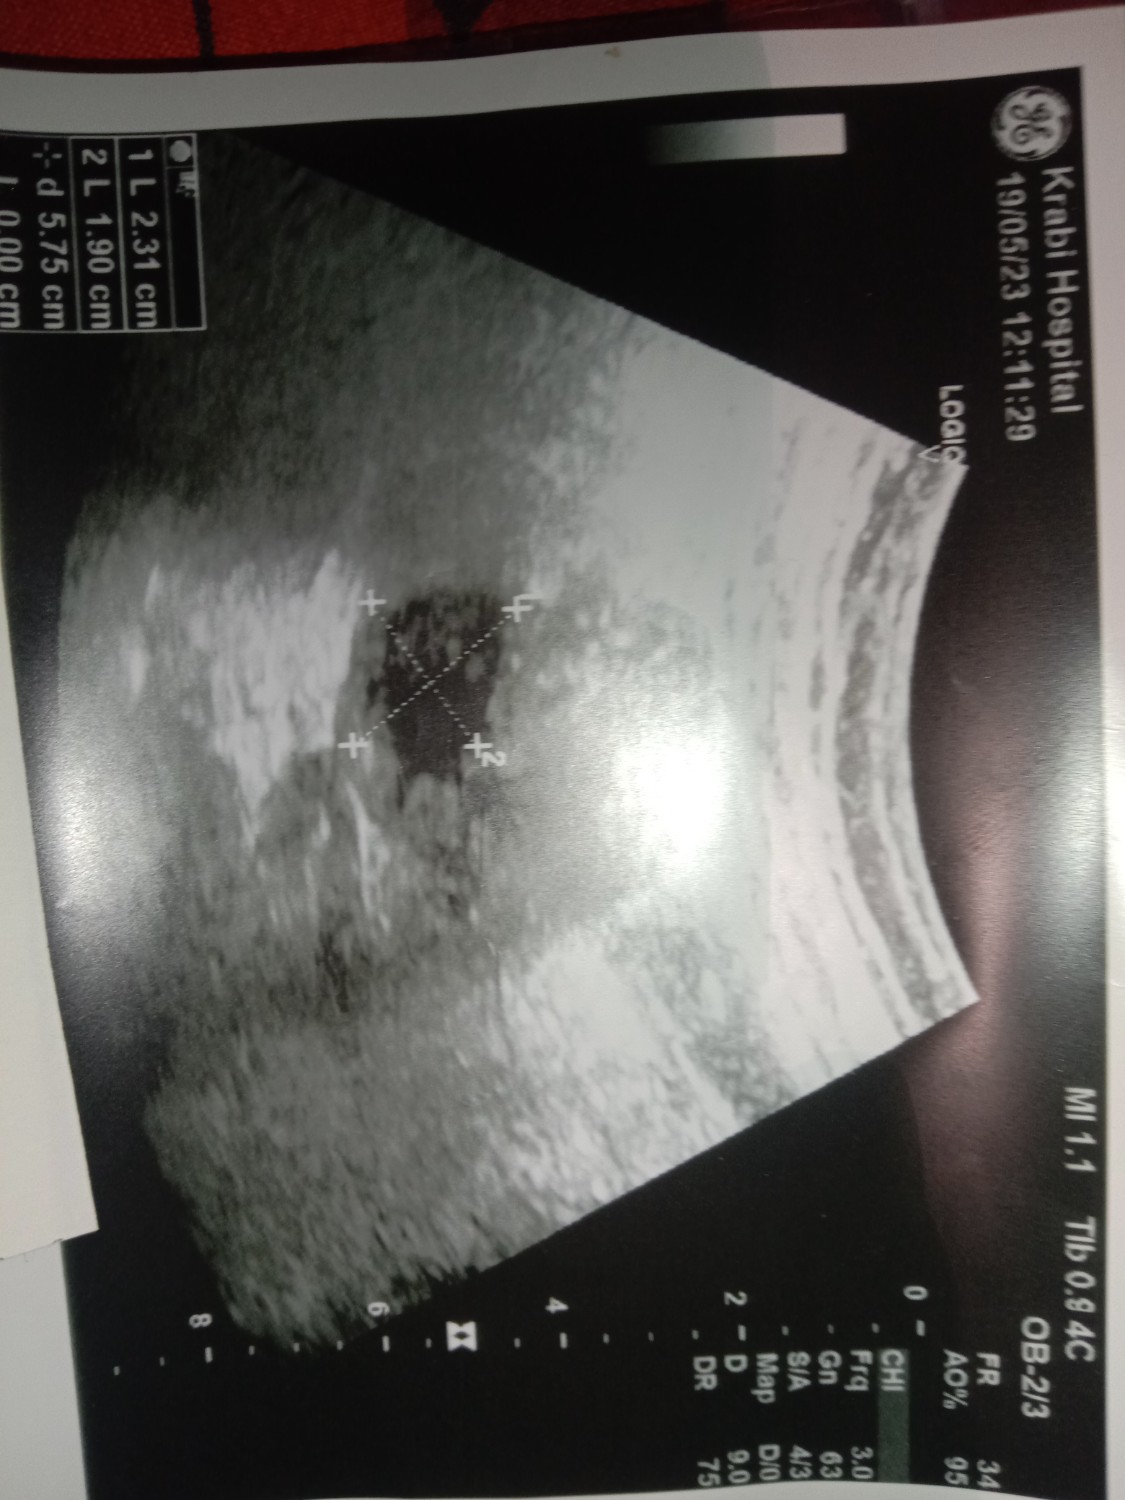

พอดีไปหาหมอเรื่องปวดประจำเดือน คุณหมออัลตร้าซาวด์ เเล้วถามเราว่าถ้าท้องจะยังไงเราก็ตอบไปว่าท้องก็เลี้ยงค่ะ เเล้วคุณหมอบอกว่าดูม่ค่อยชัดเพราะประจำเดือนใกล้มา เเล้วคุณหมอก็ให้ใบนัด คุณหมอก็ได้ให้ยาคุมมากิน ใครพอจะมีความรู้ช่วยบอกหน่อยค่ะ   หลังจากวันที่หาหมอ1วันประจำเดือนมาเเล้วก็กินยาคุมที่คุณหมอให้มาได้3เม้ดเเล้วก็หยุดกินพอประจำเดือนหยุดไป2วันก็มีเลือดคล้ายประจำ้เดือนมาเป้นสีเเดงสด ม่ปวดท้อง มา3-4วันค่ะ    อยากทราบว่าเเบบนี้ท้องใช่ม่ค่ะ มีตัวเด็กใช่ไม่ค่ะ